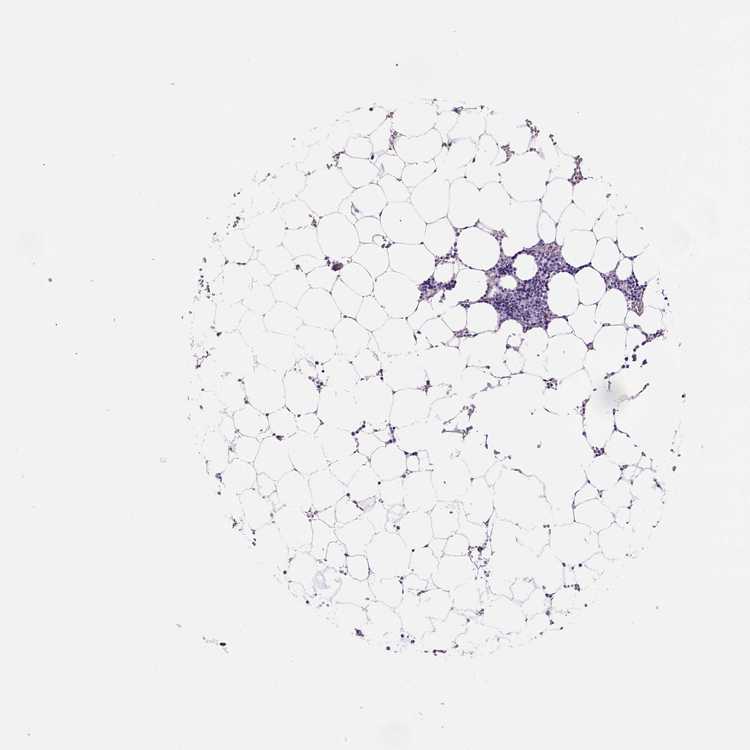

TISSUE PRIMARY DATA BONE MARROW Show tissue menu

BONE MARROW - Antibody stainingi

Antibody staining in the annotated cell types in the current human tissue is reported as not detected, low, medium, or high, based on conventional immunohistochemistry profiling in selected tissues. This score is based on the combination of the staining intensity and fraction of stained cells.

Each image is clickable and will lead to virtual microscopy that enables deeper exploration of all samples and also displays staining intensity scores, fraction scores and subcellular localization as well as patient and tissue information for each sample.

Antibody HPA074314Antibody CAB002500Antibody CAB010893

Hematopoietic cells Not detectedLowMedium